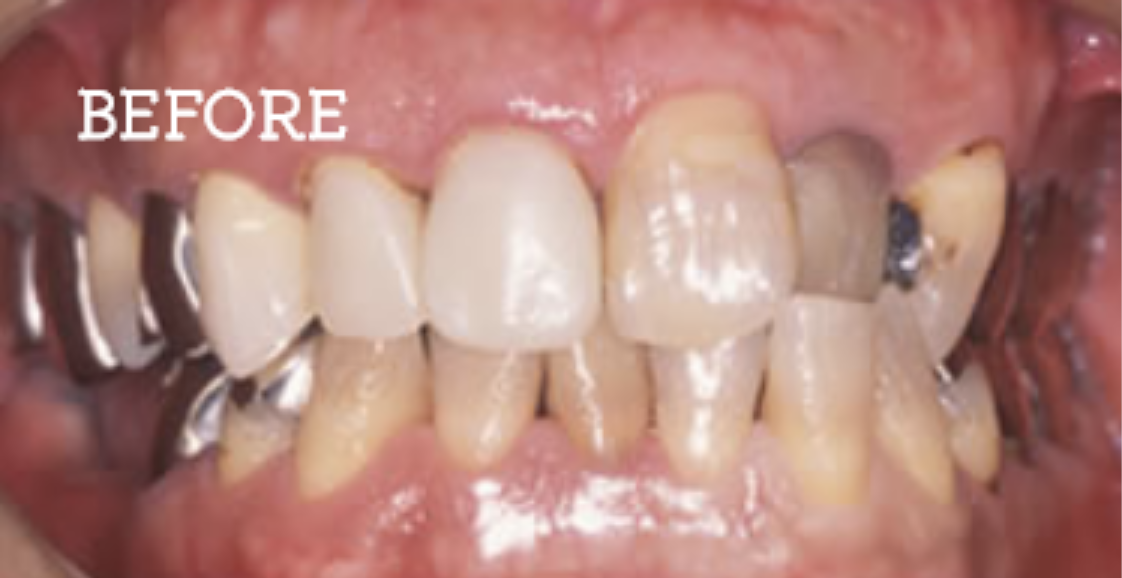

症例

お困りごとを参考に、治療のbefore・afterが確認できます。治療過程や期間、費用などを参考にご覧ください。